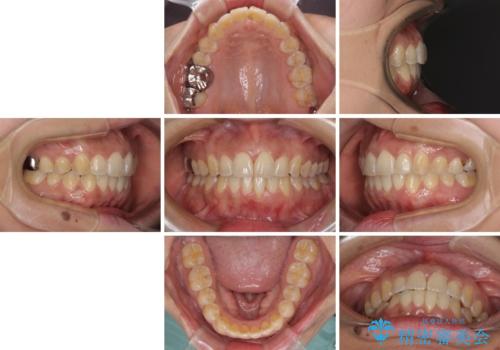

インビザラインによる狭窄歯列の拡大矯正

- 前歯のデコボコを治したいとのことで来院された患者様です。

上下顎ともに歯列全体の後方移動と側方拡大、IPR(歯と歯の間を削る)によってデコボコが解消するように設計し、インビザラインにより治療を行うこととしました。

後方移動に際し、上下の親知らずは4本とも抜歯することとしました。

治療途中で関西に転勤となってしまったため、東京に出張で来るタイミングに合わせて治療を進めることになりました。そのため、治療期間が長くなってしまいましたが、無事に仕上げることができました。